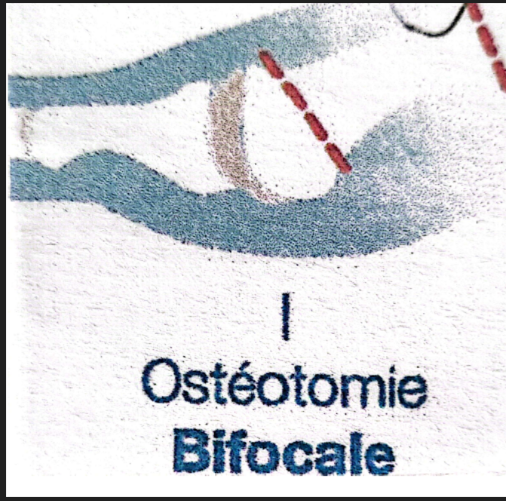

Qu’est‑ce qu’une ostéotomie bifocale percutanée ?

Figure 4 un exemple

L’ostéotomie bifocale percutanée est une technique chirurgicale mini-invasive utilisée pour traiter certains hallux valgus sévères. Elle s’adresse en particulier aux déformations importantes du premier rayon du pied, lorsqu’une seule correction osseuse ne permet pas de rétablir correctement l’alignement.

Le principe de cette intervention consiste à réaliser deux ostéotomies sur le premier métatarsien, c’est-à-dire deux sections contrôlées de l’os. Ces corrections osseuses permettent d’agir simultanément sur plusieurs composantes de la déformation afin de restaurer un alignement plus physiologique du premier rayon.

La technique est réalisée par voie percutanée, c’est-à-dire à travers de très petites incisions cutanées. Le chirurgien utilise généralement une fraise chirurgicale motorisée, introduite à travers des incisions de quelques millimètres seulement. Cette approche permet de travailler directement sur l’os tout en limitant les traumatismes des tissus mous environnants, comme les muscles, les tendons et la capsule articulaire.

Deux niveaux de correction peuvent être effectués au cours de l’intervention.

Première correction

La première est une ostéotomie proximale, réalisée à la base du premier métatarsien. Elle permet de corriger l’angle inter-métatarsien, c’est-à-dire l’écartement anormal entre le premier et le deuxième métatarsien. Cette correction agit sur l’une des causes principales de la déformation.

Figure 5 : sièges des ostéotomies, métaphyse proximale et métaphyse distale

Deuxième correction

La seconde est une ostéotomie distale, réalisée au niveau de la tête du premier métatarsien. Elle vise à améliorer l’alignement du gros orteil et à repositionner l’articulation métatarso-phalangienne dans un axe plus anatomique.

L’association de ces deux corrections permet de réaligner l’ensemble du premier rayon du pied, en agissant à la fois sur la position du métatarsien et sur l’orientation du gros orteil.

L’objectif de cette technique est non seulement de corriger la déformation, mais aussi de préserver la mobilité articulaire et de restaurer une mécanique du pied plus équilibrée lors de la marche.

Figure 6 : La correction axiale percutanée, est réalisée par une mèche-fraise de Shanonn, introduite par une incision de 2 à 3mm et qui effectue une « fragilisatiuon osseuse « au niveau métaphysaire, laissant un pont osseux . Puis par une « manœuvre manuelle » externe, le chirurgien exerce une pression externe qui se fait du pont osseux qui agit comme une chanrière pour corriger de quelques degrés la dévéiation axiale .

L’approche percutanée présente plusieurs avantages. ( figure 6) Les incisions cutanées sont très petites, ce qui réduit la taille des cicatrices et limite l’agression des tissus mous. Cette approche peut également contribuer à diminuer la douleur postopératoire et à faciliter la récupération fonctionnelle, tout en permettant une correction précise de la déformation.

En résumé, l’ostéotomie bifocale percutanée permet d’apporter une correction globale de l’hallux valgus sévère, en intervenant simultanément sur plusieurs paramètres anatomiques responsables de la déformation.